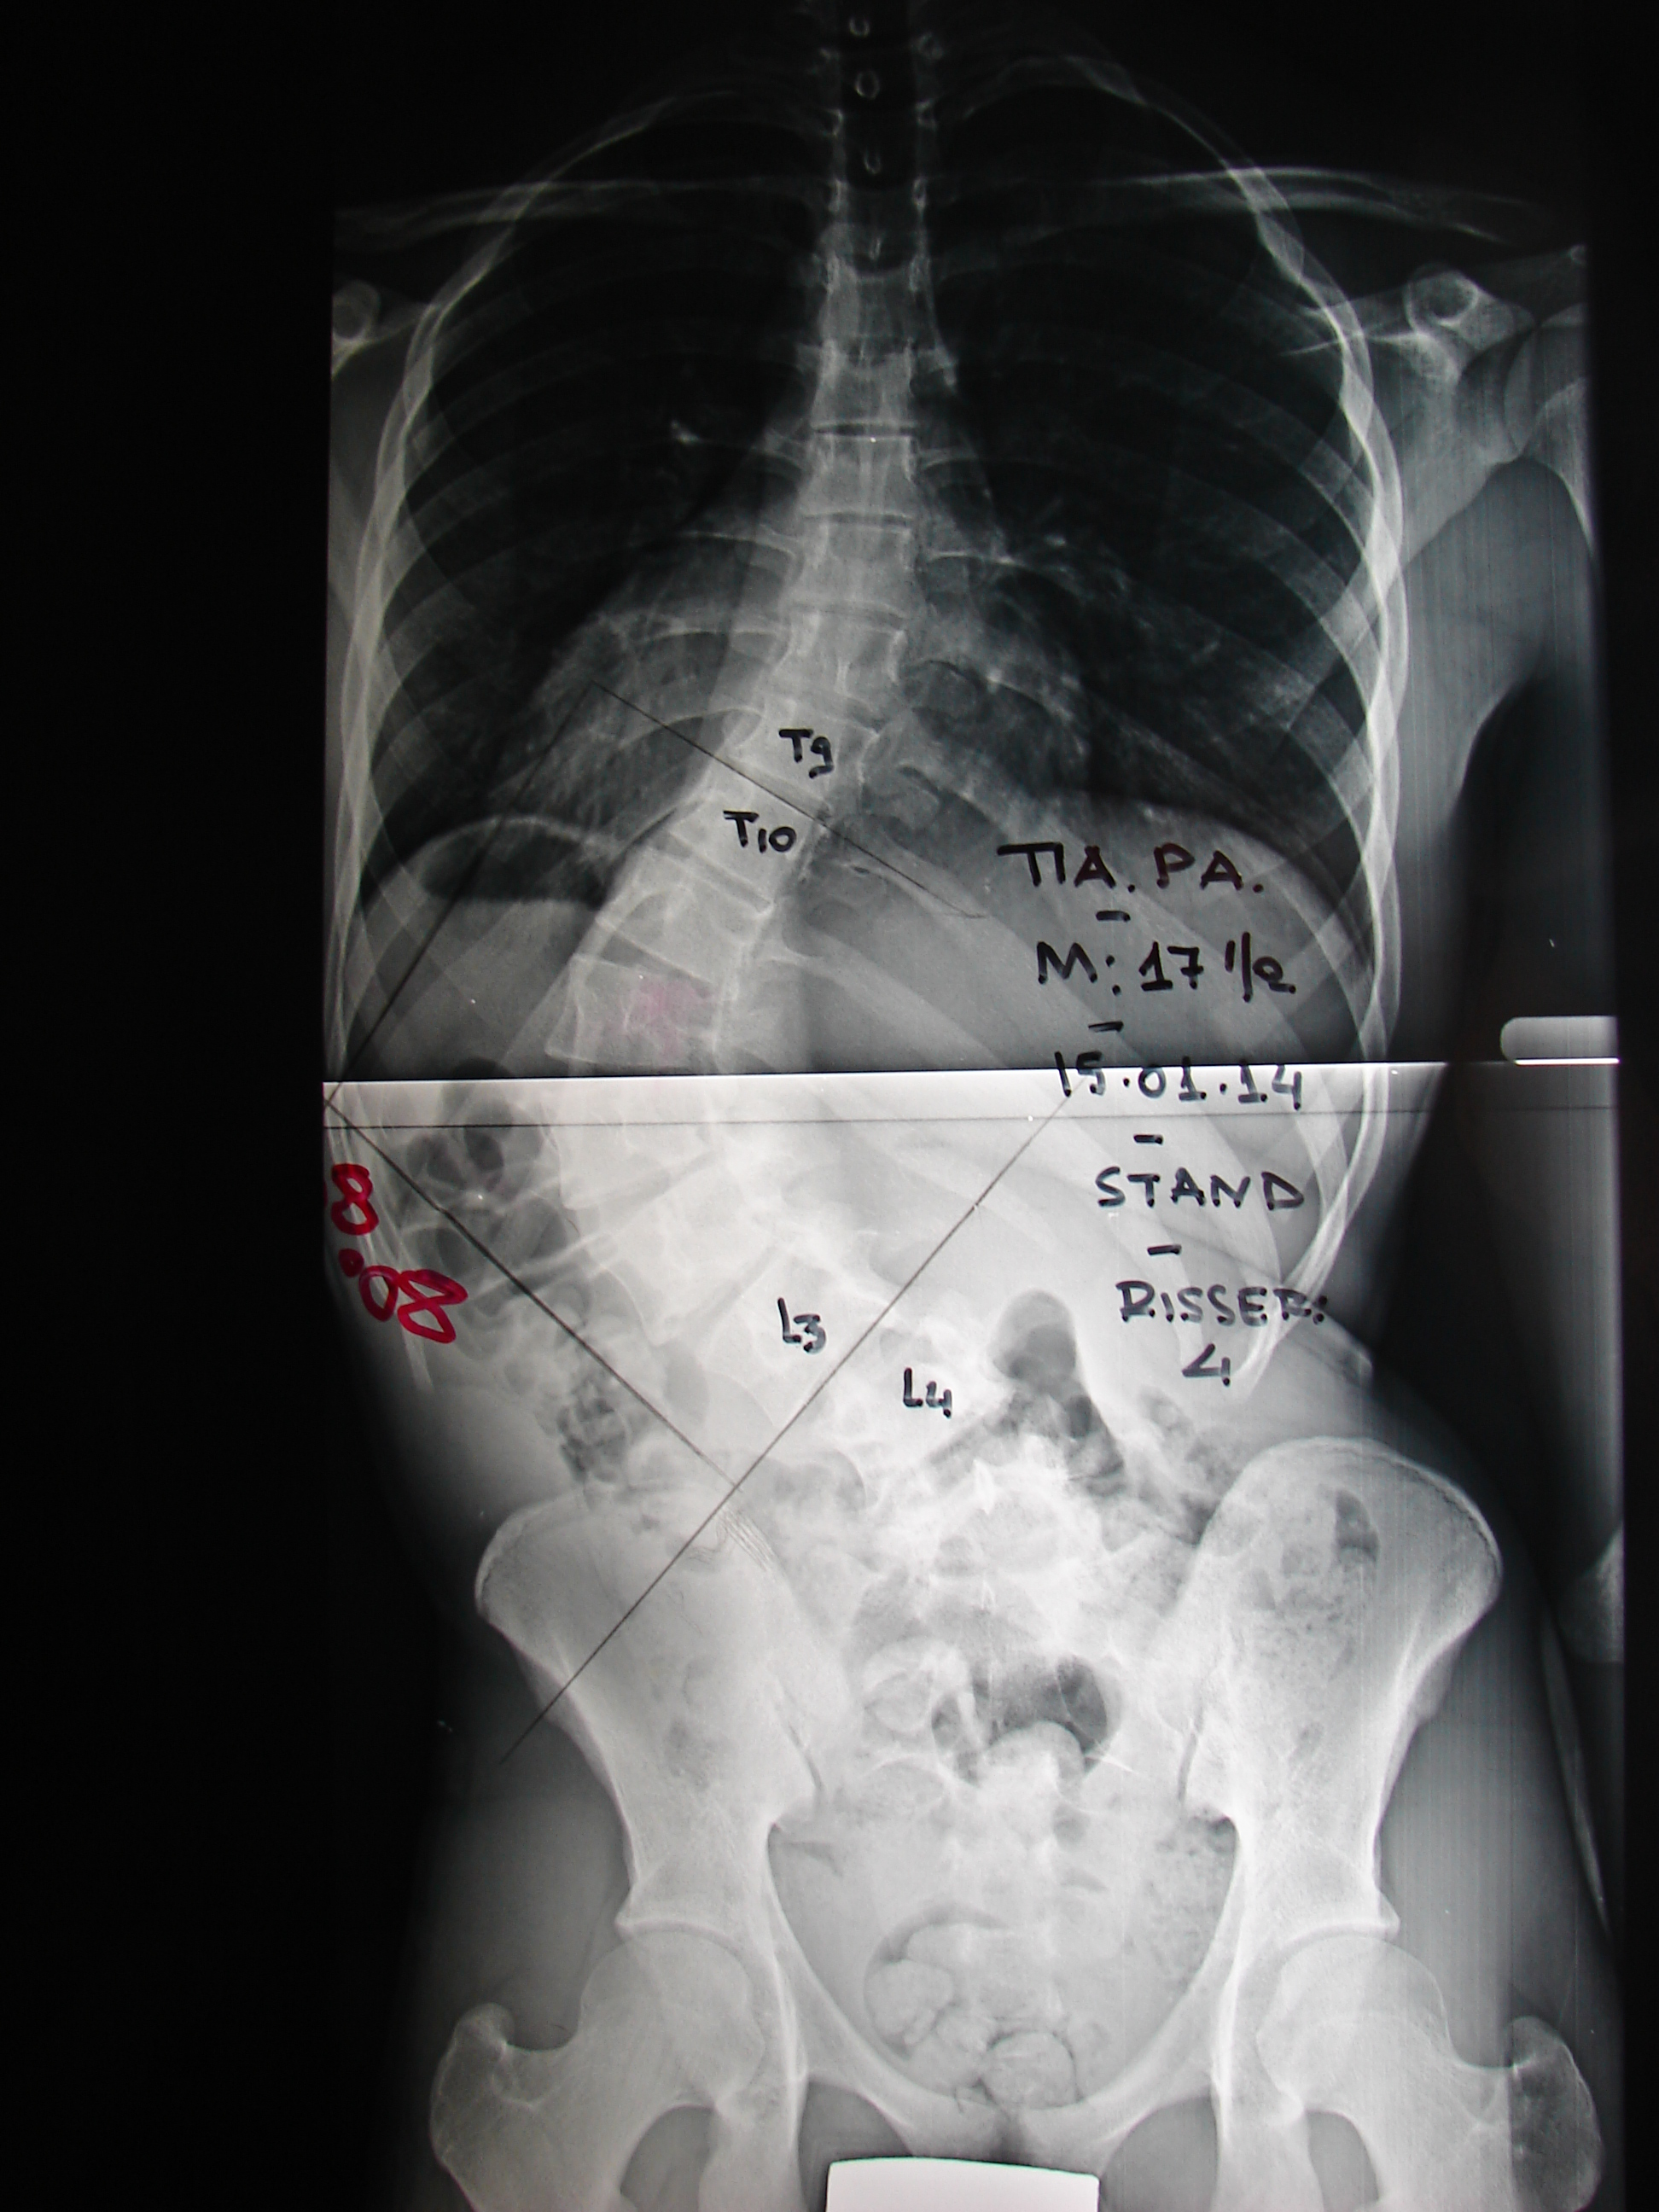

Εικόνα 2 α,β,γ,δ,ε

Οι ακτινογραφίες της σπονδυλικής στήλης δείχνουν την προοδευτική επιδείνωση της σκολιώσεως απο την των 15 ετών μέχρι των 18. Η σκολίωση είναι αριστερή θωρακοσφυϊκή (Θ10-ο3). Στην ηλικία των 15 ετών ήταν 30 μοίρες και στην ηλκία των 18 ήταν 86 μοίρες .